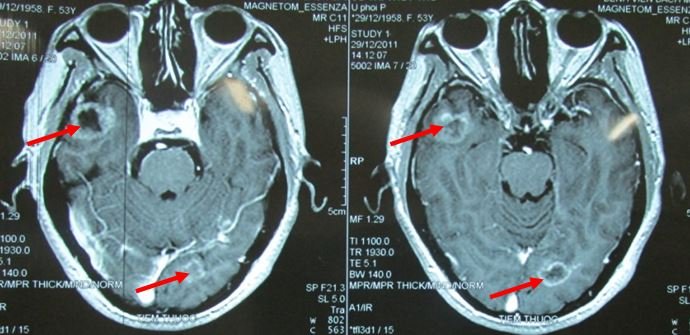

- Chụp MRI sọ não

Hình 2: hình ảnh chụp MRI sọ não cho thấy di căn não đa ổ